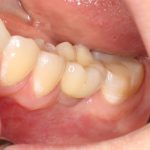

Рекомендации по установке имплантов. Для всех. Часть III